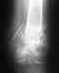

мне поставили диагноз "Разрыв дистального межберцевого слидесмоза". Подскажите пожалуйста обязательна ли при таком диагнозе операция и что она из себя представляет?

Операция тут, конечно, не по жизненным показаниям. но без нее большие шансы, что вилка голеностопного сустава будет нестабильна, то есть будут постоянные боли при ходьбе. Методик операций несколько, смысл в том, чтобы тем или иным устройством сблизить и удержать берцовые кости до рубцевания синдесмоза. При застарелом повреждении, т.е. при отсрочке операции более 2-3 недель, этого уже может быть недостаточно, может потребоваться пластика синдесмоза каким-либо материалом.